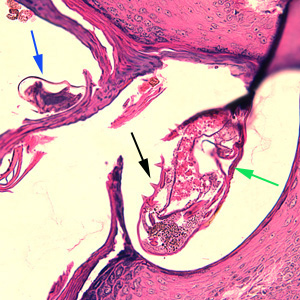

Cilt biyopsisinde uyuz akarı (işaretli)

Cilt Biyopsisinde Uyuz Akarı (İşaretli)

Cilt biyopsisinde görülen Sarcoptes scabiei akarı ve yumurtası. Bu görüntüde hem yetişkin akar hem de yumurta görülebilmektedir.

Kaynak: CDC (Hastalık Kontrol ve Önleme Merkezi)